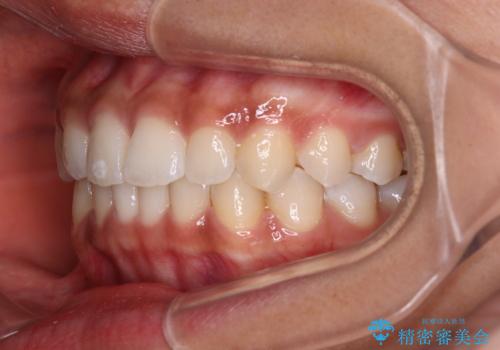

前歯のデコボコを治したい インビザライン・モデレートによる矯正治療

- 上下前歯の叢生を気にして来院された患者様です。

インビザラインでの治療を希望されていて、デコボコの程度が中等度であり、安価なパッケージにて対応可能と判断されたため、インビザライン・モデレートを用いて矯正治療を行うこととしました。